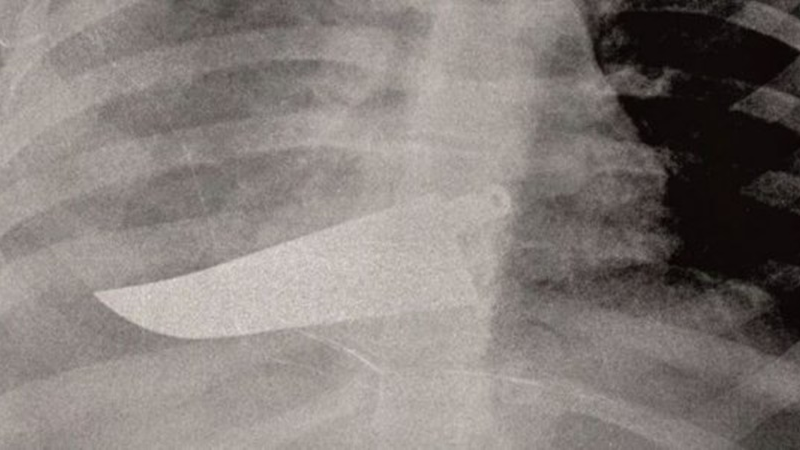

Οι ακτινογραφίες που «μιλούν» για τις κακοποιημένες γυναίκες (pics)